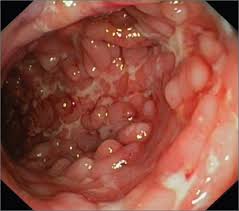

Pictured here is the appearance the colon can take in a patient with Crohn's disease

Cobblestoning